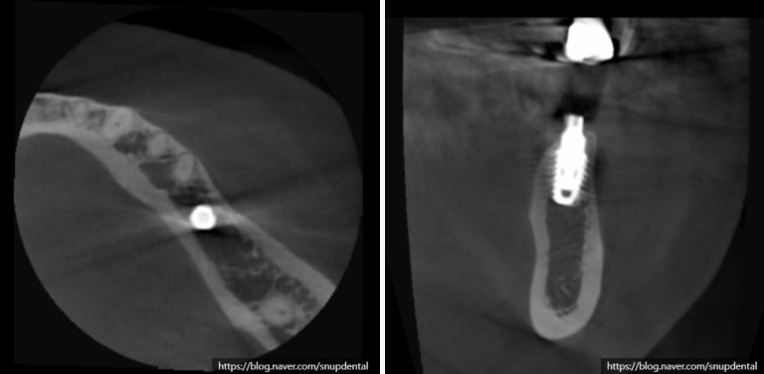

부분 CT 상에서 현재 뼈 상태 및 임플란트 식립 계획을 세워봅니다.

임플란트 수술 후 구강 내 사진 및 부분 CT 캡처 사진입니다

부분 CT를 촬영하여 현재 치조골 상태 확인 및 임플란트 수술 계획을 잡고

임플란트 수술 후 부분 CT 및 구강 내 사진